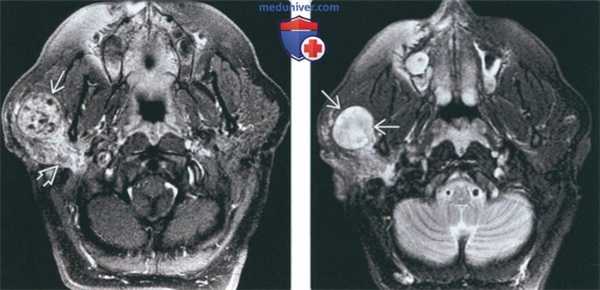

(Слева) МРТ Т1ВИ FS с КУ, аксиальная проекция. У переднего края поверхностной доли правой околоушной железы определяется округлое образование 0. Имеются участки неоднородного накопления контраста с включениями кист. Обратите внимание, что закупорка выводного протока опухолью привела к развитию паротита.

(Справа) МРТ Т2ВИ FS, аксиальная проекция. Визуализируется округлое образование с неоднородным сигналом высокой интенсивности, которое расположено в области переднего края поверхностной доли околоушной железы. Отличить такое образование от доброкачественной смешанной опухоли, которая встречается гораздо чаще, практически невозможно. (Слева) КТ с КУ, аксиальная проекция, выполненная у пациента с нейрофиброматозом 2 типа. В области переднего края поверхностной доли околоушной железы имеется округлое образование размером менее 1 см. Шваннома неравномерно накапливает контраст, но из-за небольших размеров участки кистозного перерождения отсутствуют.

(Слева) На аксиальной МРТ (Т1 ВИ С+ FS) в передних отделах поверхностной доли околоушной железы визуализируется округлое объемное образованней Опухоль неравномерно накапливает контраст, видны разбросанные кистозные участки. Обратите внимание на паротит обусловленный обструкцией протока шванномой.

(Справа) На аксиальной MPT (Т2 ВИ FS) в передних отделах поверхностной доли околоушной железы визуализируется опухоль округлой формы с неоднородным гиперинтенсивным сигналом. Такое новообразование сложно отличить от значительно более частой доброкачественной смешанной опухоли.